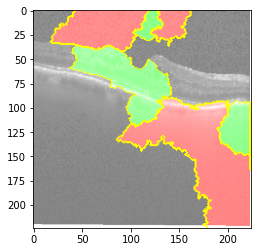

Original Image

Explanation B

Explanation C

Explanation D

GradCAM

Original Image

Explanation B

Explanation C

Explanation D

GradCAM

Original Image

Explanation B

Explanation C

Explanation D

GradCAM

Fig 6, 7, 8 and 9 depicts the visualization of correct predictions by our proposed CNN model where fig 6 is class CNV, fig 8 is class DME, fig 7 is DRUSEN and finally, fig 9 is NORMAL. Here the first photo in every class is the original image. The LIME map of our suggested model’s prediction is shown in image B whereas in image C the positive region is highlighted in specific sections on the original image. For Image D we have increased the number of features from 5 to 10 thus more regions have been predicted as the positive region which is highlighted in green. After increasing the features from 5 to 10, some of the regions are predicted wrongly. The red regions represent the output of incorrect prediction. The following image represents the Grad-CAM heatmap highlighting the regions with our model’s prediction.